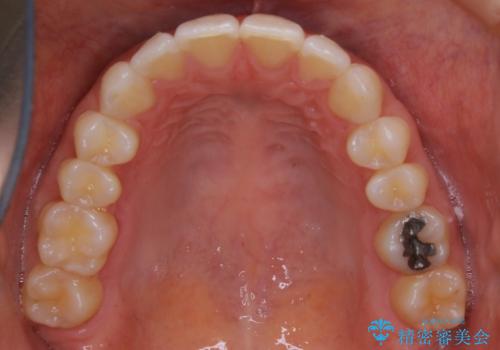

- 下の前歯のがたつきが気になるとの事でご相談にいらした患者様です。

元々はリンガルブラケットをご希望されていましたが、モニター制度を利用してインビザラインによる治療を行いました。

インビザラインFULLで奥歯の噛み合わせから改善させることで、上下の真ん中位置をしっかり合わせることが出来ました。

横顔のシルエットも改善させることができ、大変喜んでいただけました。